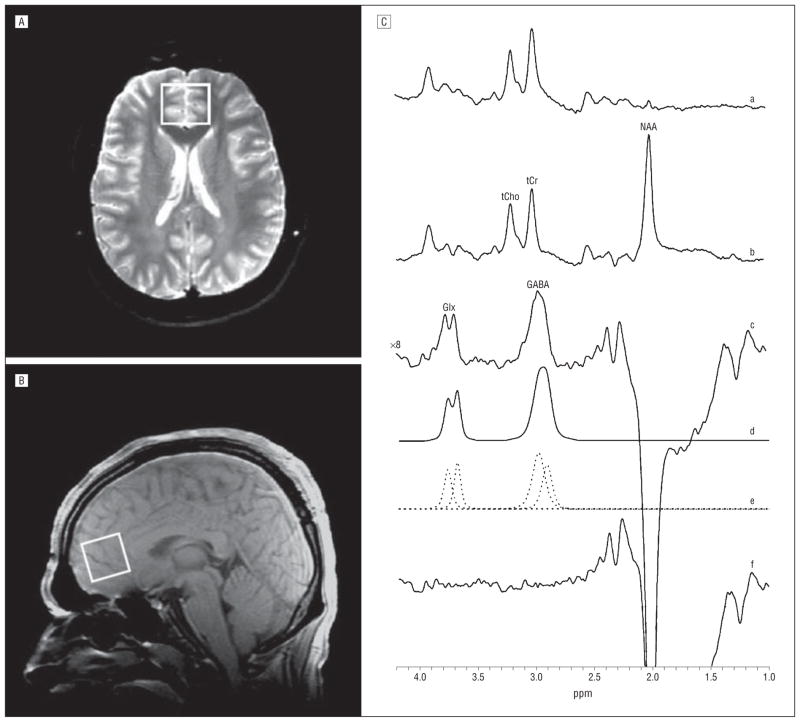

The GABA-edited 1H MRS spectra were acquired using the standard J-editing difference method,33 as modified by Sailasuta et al34 and recently fully described,35 with an 8-channel phased-array head coil for signal detection. The scanner’s body coil was used to excite all the 1H signals (580 excitations) in a single 2.5×2.5×3.0-cm3 voxel in the ACC (Figure 1A and B). Using the standard J-editing technique,33 GABA detection is achieved by applying a frequency-selective inversion pulse that avoids excitation of the GABA C-3 peak at 1.9 ppm on alternate scans (Figure 1C, parts a and b), with a repetition time of 1500 milliseconds and an echo time of 68 milliseconds. This results in selective inversion of the outer lines of the C-4 GABA triplet resonance at 3.0 ppm on alternate scans by, respectively, inhibiting and allowing its J-modulation. Subtracting the 2 subspectra thus acquired yields the GABA difference spectrum, consisting of the outer lines of the GABA C-4 triplet at 3.0 ppm, while the much stronger overlapping total creatine resonance, a singlet that is not J-modulated, is eliminated (Figure 1C, part c). While this pulse sequence is optimized for GABA detection, it also achieves detection of the combined resonances of Glx at 3.7 ppm (Figure 1C, part c) because of their high structural, chemical, and magnetic similarities with GABA.

Figure 1.

Axial (A) and sagittal (B) images showing anterior cingulate cortex voxel size and location and volume-selective point-resolved spectroscopy proton magnetic resonance spectra (C) with the editing radiofrequency pulse on (a) and off (b). With the editing pulse off (b), a standard point-resolved spectroscopy spectrum is obtained, which yields high-quality spectra for N-acetylaspartate (NAA), total creatine (tCr), and total choline (tCho) in the anterior cingulate cortex. The difference of the spectra in parts a and b showing the edited γ-aminobutyric acid (GABA) and combined resonances of glutamate and glutamine (Glx) peaks (c), with the best-fit model curve of the edited spectrum (d), the individual components of the best-fit curve (e), and the residuals of the difference between the edited (c) and best-fit (d) spectra (f ). The data were acquired in 15 minutes from a 2.5 ×2.5 ×3.0-cm3 voxel using a repetition time of 1500 milliseconds, echo time of 68 milliseconds, and 290 interleaved excitations (total, 580) with the editing pulse on or off.